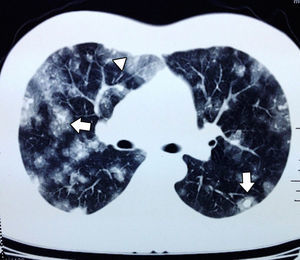

In September the patient presented with haemoptysis and dyspnoea, and was admitted to a private hospital, where a computed tomography (CT) chest scan was indicated (Fig. 2). A bronchoscopy was performed and cultures and biopsies were taken, which tested negative for malignancy, tuberculosis or fungal infection. Plain and contrasted CT scan of the abdomen was indicated which showed multiple, rounded lesions, hypodense in the liver graft (Fig. 3); CT scan-guided biopsy was performed which tested negative to malignancy.

Angiosarcoma presents with early metastasis to other organs such as the lung, spleen or bone.10 In plain chest X-rays there may be diffuse infiltrations. The most common findings in CT chests scans indicated for angiosarcoma metastasis are multiple solid tumours. When they present with haemorrhaging they result in a ground-glass opacity imaging known as a halo sign and this occurs in 32% of patients. To a lower extent cystic changes may be found in the thin walls (13%) which when distributed in the pleural cavities increase the incidence of pneumothorax or haemothorax.12